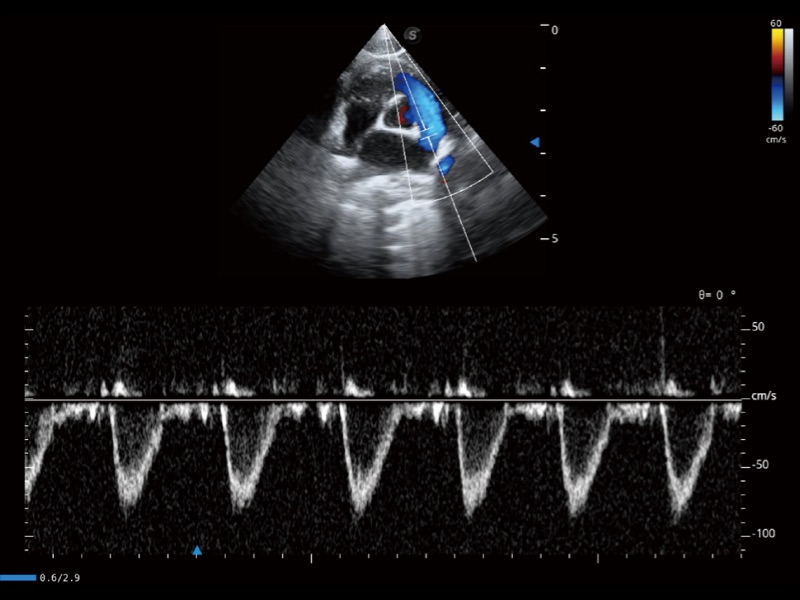

通过创新的 Matrix E自适应滤波器和超长时间域算法,极大提升超低速微细血流的检出能力,同时更精准地滤除软组织和噪声信号,为兽用医生提供以往无法通过常规血流获得的疾病诊断信息。

通过色彩血流和实时宽景相结合,可观察到完整的静脉或动脉的血流,方便医生检查。实时扫查过程中,如有任何操作失误也可以很容易地进行回扫擦除,而不会中断扫查。

通过360度任意调节3条M型取样线,在同一心动周期上观察心脏不同位置的运动曲线,得到准确的心功能测量数据,有效评估心肌运动及左心室功能。